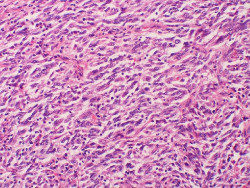

Descubren un gen que impide el desarrollo de la metástasis en el cáncer

Investigadores de la Universidad de Ginebra (UNIGE), en Suiza, han identificado un gen que impide el desarrollo de la metástasis, lo que permitirá a la ciencia apuntar a las metástasis de manera más efectiva gracias a este nuevo enfoque que tiene en cuenta la enorme heterogeneidad y los fenotipos de las células tumorales.